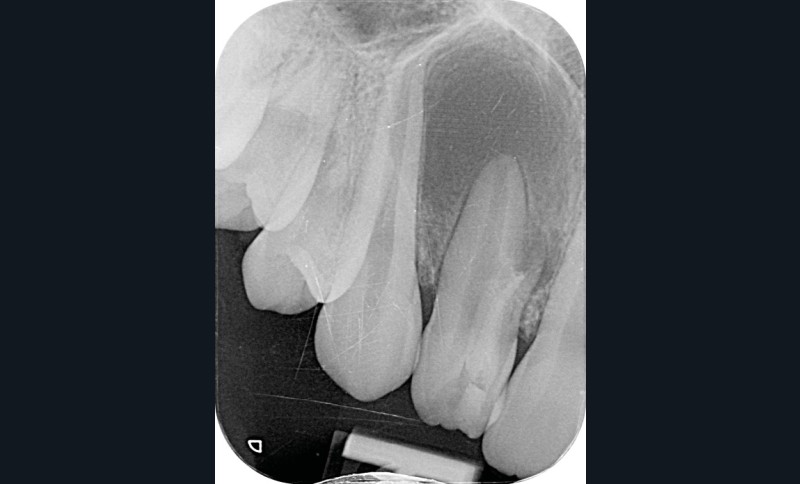

La patiente, âgée de 12 ans, s’est présentée à ma consultation avec une demande du chirurgien de réaliser le traitement endodontique de la 12 avant le curetage sous anesthésie générale. La radiographie périapicale préopératoire a mis en évidence une anatomie complexe. Les tests préopératoires ont montré un sondage parodontal sain, une percussion positive et un test au froid positif. La patiente présentait également une fistule vestibulaire active. Le Cone Beam a mis en évidence la présence d’une dens in dente et d’une lésion imposante ainsi qu’une palatoversion importante de la racine de la 12. La lésion est-elle responsable de ce mouvement dentaire ? (fig. 1, 2 et 3).

Le test au froid et la position de la lésion m’ont permis de prendre ma décision thérapeutique. En effet, la lésion située uniquement sur la face vestibulaire de la dent en regard de l’apex du canal de la dens in dente et la persistance d’un test au froid positif à travers chacune des séances de soins m’ont permis de m’assurer que la dent principale était bel et bien vivante.